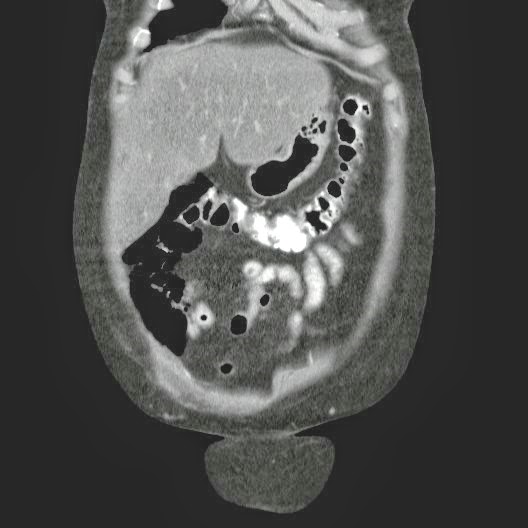

Caso Interesante #4

Adulto masculino, 1 semana de fiebre y malestar general.

¿Dónde esta ubicado el hallazgo?